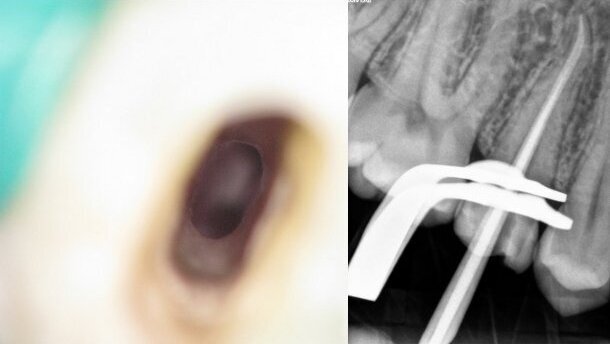

Truớc khi điều trị, bệnh nhân được chụp một phim Xquang mới (hình 1). Trên phim chúng ta thấy không chỉ một mà là hai phần dụng cụ gãy trong mỗi ống tủy gần. Bắt đầu quá trình điều trị, răng được cách ly bằng đê cao su, và chất hàn miệng ống tuỷ được lấy ra. Trước hết cần tạo ngay một đường vào để tiếp cận và nhìn thấy phần dụng cụ gãy. Sử dụng mũi Gates-Glidden (DENTSPLY Maillefer) mở rộng miệng ống gần.

Sau khi tiếp cận được phần dụng cụ gãy trong ống gần ngoài, tôi làm biến đổi phần đầu của cây Gates-Glindden (hình 2).

Bằng cách này, tôi đã tạo ra một đầu khoan có khả năng tạo một đường vào phía trên phần dụng cụ gãy. Lúc này, ta đã có thể nhìn thấy phần dụng cụ gãy (hình 3). Sau đó, sử dụng sóng siêu âm nới lỏng dụng cụ trong lòng ống tuỷ. Cả hai đầu ProUltra (DENTSPLY Maillefer) bằng zircronium nitride và titanium cùng được sử dụng. Sau 1 tiếng ruỡi, phần dụng cụ đã được nới lỏng ra nhưng vẫn bị tắc lại trong ống tủy. Chúng tôi quyết định để lại và hẹn bệnh nhân đến lần sau. Paste canxi hydroxide (UltraCal XS, Ultradent) được đặt vào phần miệng 2 ống tủy gần, phía trên đặt một viên bông vê nhỏ và hàn lại bằng GIC (Fuji IX GP Fast, GC).